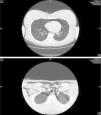

Chest CT scan showed a large pneumomediastinum with bilateral pneumothorax (Fig. 1).